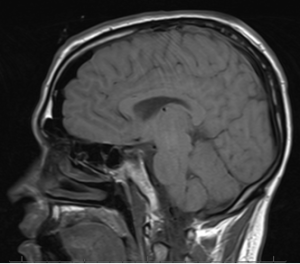

I finally requested my MRI scans from UT Southwestern. At first they said no, then I said please and NO ONE, not even fancy hospitals can deny a request when you utter the magic word.

Moving on, I received said scans in the mail a few days ago and have selected a few to show you.

This first one was done on the 24th of May, in that foul year of our Lord, 2009. The white spot on my brainstem is White Out (this blog brought to you by Bic). My hands were all wet one day and I needed to write something down (I needed more toilet paper, I think). The next best place to scribble a quick note? Obviously, the brainstem. After I got TP I didn’t need the note anymore so I whited it out.

I jest. It’s actually the cavernoma, the white emanating from it is Whi…blood